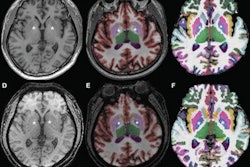

Contador and colleagues explored whether there was any association between baseline MRI exam findings in early-onset Alzheimer's patients that indicate global atrophy and cognitive outcomes over a two-year period. Their study included 48 people with early-onset Alzheimer's disease and 42 healthy controls, all of whom underwent MRI exams, lumbar punctures, and neuropsychological assessments, then annual cognitive assessments over a two-year period.

The team found that, at baseline MRI exam, cortical thickness in both left and right hemispheres was lower and lateral ventricle volumes were higher in the early-onset disease cohort, and that these results were associated with poorer overall cognition, language, and attention/executive functioning two years later (p < 0.0028).

Lower regional cortical thickness also negatively affected most cognitive outcomes except for verbal and visual memory, and higher amygdalar volume had a negative influence on patients' letter fluency. Contador and colleagues did not find significant association with baseline hippocampal volume in early-onset Alzheimer's patients over the two years of annual evaluation.